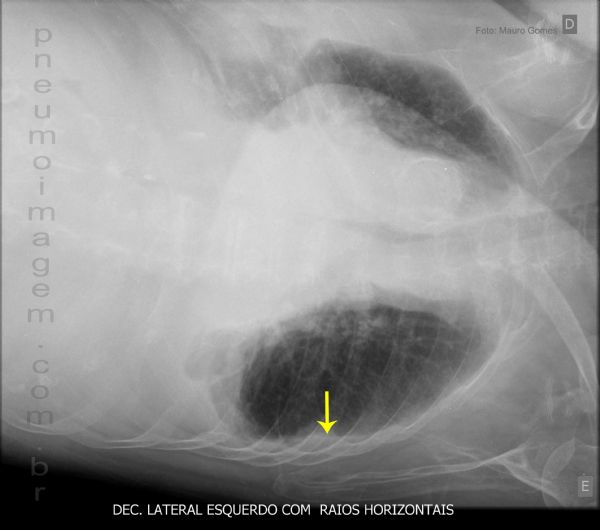

Todo derrame pleural que produza uma lâmina de líquido (seta amarela) que escorreu maior que um centímetro na incidência em decúbito lateral com raios horizontais indica a presença de derrame passível de ser puncionado e analisado, pois o quadro clínico/radiológico isoladamente não é suficiente para a distinção entre os derrames pleurais simples e os complicados ou empiemas.

All pleural fluid that flowed to produce a line (yellow arrow) greater than one centimeter in lateral incidence with horizontal rays indicates the presence of fluid that can be punctured and analyzed because the clinical / radiological alone is not sufficient to distinguish between the pleural not complicated and complicated or empyema.